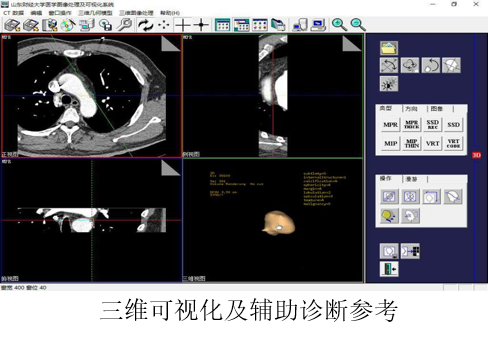

目前,利用CT数据进行肺结节/肿瘤的自动提取与辅助诊断对于临床早期肺癌的诊疗意义重大。为了有效提高诊断结果的可重复性和对于图像、疾病解释的一致性,课题组研发了该系统,满足了肺部病灶区域分析及辅助诊断、符合医生操作习惯的实时功能需求,在医学图像去噪、超分辨重建、病灶区域分割及三维可视化、矩阵快速求解及优化等关键技术方面取得了理论创新和关键技术突破。

系统已经在山东省千佛山医院、山东省医学影像学研究所、烟台毓璜顶医院等十余家医院及科研院所推广应用,有效地辅助临床医生对病灶组织进行定量乃至定性分析,经济/社会效益显著,获得山东省科技进步一等奖。系统研发工作得到了国家自然科学基金、山东省重点研发计划的支持,相关成果获得授权发明专利5项、软件著作权8项、发表学术论文22篇。